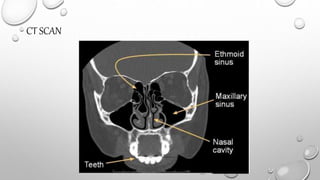

COMPUTERIZEDTOMOGRAPHY (CT) & MAGNETIC

RESONANCE IMAGING (MRI)

• THESE MODALITIES PROVIDE MULTIPLE SECTIONS THROUGH THE

SINUSES AT DIFFERENT PLANES AND THEREFORE CONTRIBUTE TO

THE FINAL DIAGNOSIS AND THE DETERMINATION OF EXTENT OF

THE DISEASE.

CT SCAN

MRI